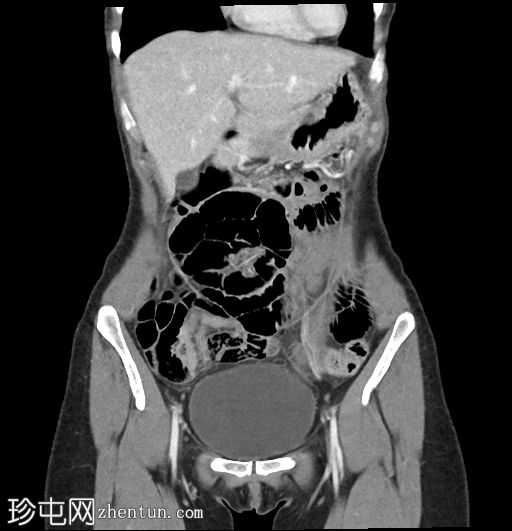

冠状位增强扫描(门静脉期)

左肾肾盂肾盏系统及左侧输尿管,管壁环周增厚及强化,符合肾盂输尿管炎的影像学表现

左肾实质强化正常,无肾周脂肪浸润

膀胱充盈良好,无管壁增厚或周围脂肪浸润

无尿路结石

偶然发现肠系膜有一2.2 x 4 x 3.2 cm大小的边界清晰的均匀脂肪密度病变,符合肠系膜脂肪瘤的影像学表现

左侧卵巢静脉明显